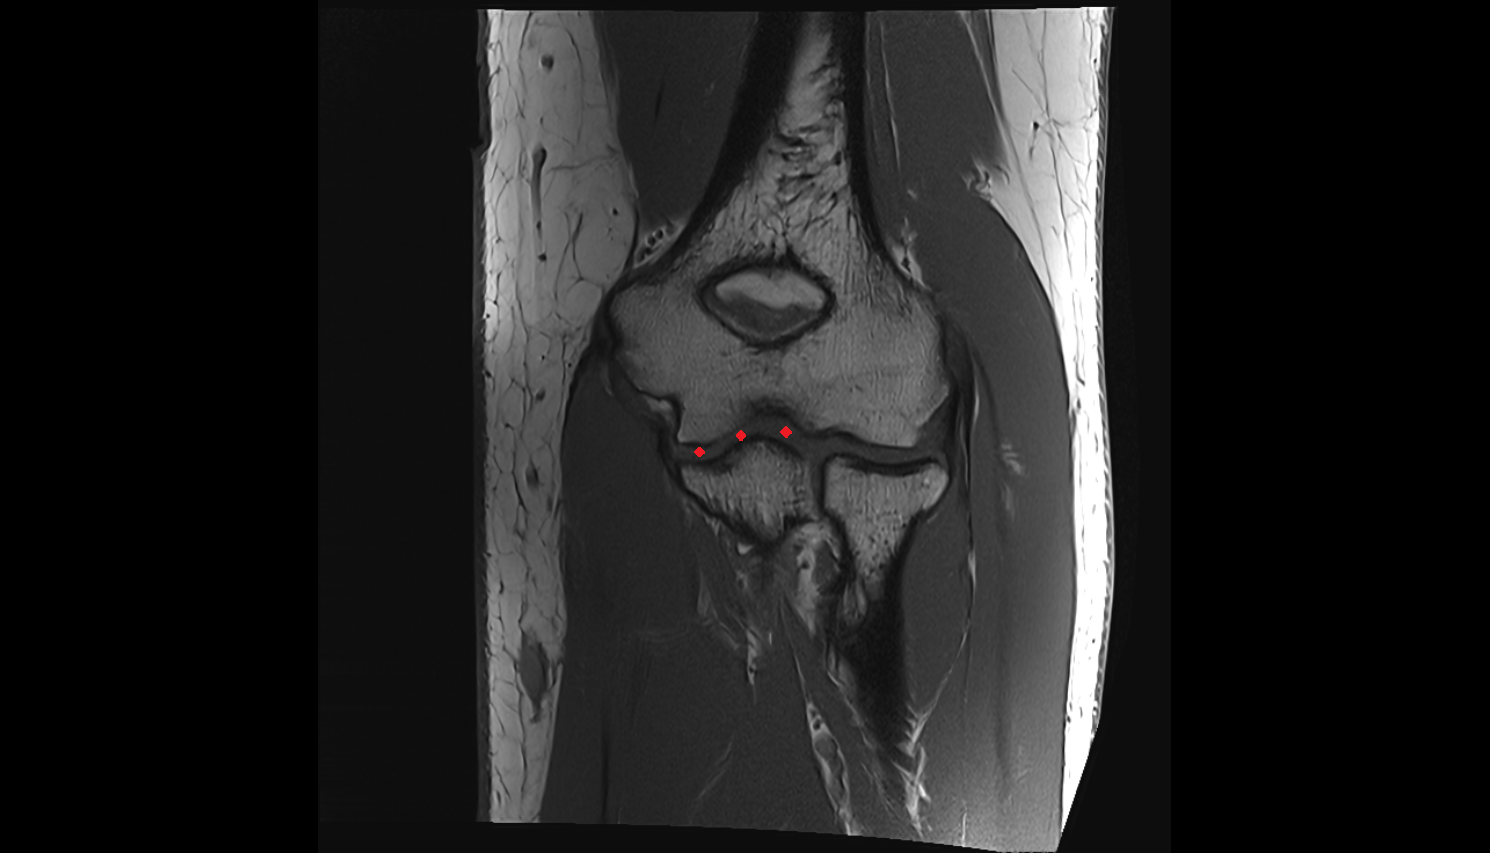

- Knee Joint